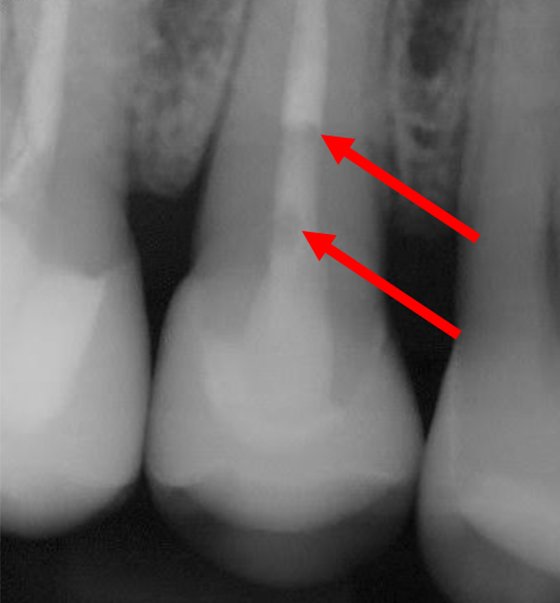

This discolored right central incisor will receive an inside-out bleaching technique after endodontic therapy. This radiograph of the discolored tooth shows a thin bonded layer of flowable covering the gutta percha to protect the seal during the inside-out bleaching protocol.